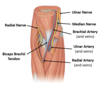

boundaries of the cubital fossa

brachioradialis, pronator teres, line across lateral/medial epicondyles

what passes through the cubital fossa

tendon of lateral biceps brachii, brachial artery, median nerve

what is in the superficial cubital fossa?

cephalic vein, median cubital vein, basillic vein

what is in the deep cubital fossa?

radial nerve, ulnar nerve, median nerve, brachial artery and veins, ulnar artery and veins, radial artery and veins, biceps brachii tendon